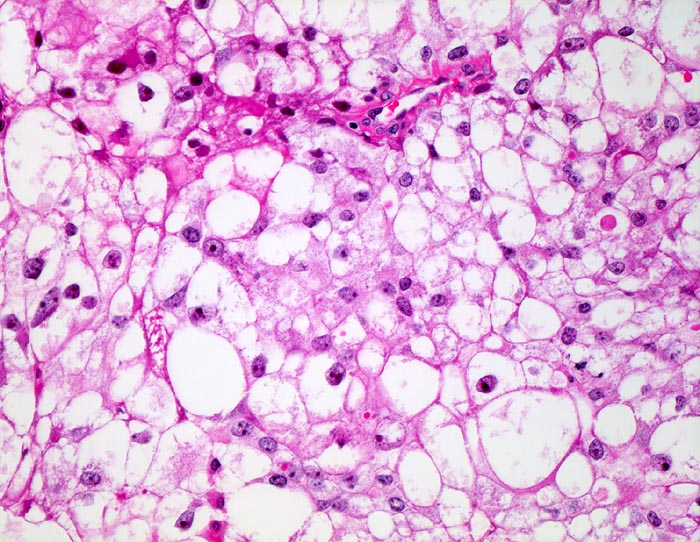

PathoPic – image database / PathoPic ID 4890 - mässig differenziertes hellzelliges Nierenzellkarzinom

mässig differenziertes hellzelliges Nierenzellkarzinom

Tumorzellen mit deutlichen Zellgrenzen. Das reichlich vorhandene Zytoplasma ist entweder klar oder fein granulär eosinophil. Die Zellkerne sind polymorph, deutlich grösser als Zellkerne eines Nierentubulus und enthalten schon bei schwacher Vergrösserung gut erkennbare Nukleolen entsprechend einem mässig differenzierten Karzinom.

Beim hellzelligen Nierenzellkarzinom erfolgt die Gradierung entsprechend der Kernmorphologie. Die meisten Karzinome fallen in die Kategorie der mässig differenzierten G2 Tumoren. Hoch differenzierte G1 Tumoren haben kleine runde Kerne mit feinen Nukleolen. Mitosen sind kaum nachweisbar. Bei wenig differenzierten G3 Karzinomen lassen sich neben stark vergrösserten hyperchromatischen Kernen mit stark vergrösserten Nukleolen auch mehrkernige Zellen nachweisen.